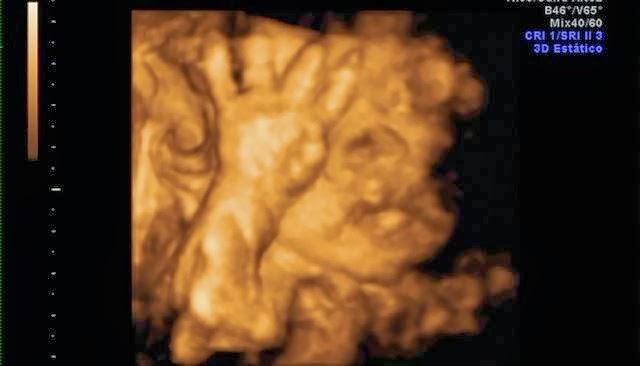

Su carita!Y estas son algunas capturas de pantalla de la eco 4d que me hice a principios de mes. Que ya de paso decir, que esta no me gustó NADA!! Tuvimos que esperar 2 horas para que nos cogieran, la eco nos la hicieron con prisas, y sólo se le vió la mitad de la cara.. así que para habernos gastado 100€ muy mal!! No os recomiendo la Ginecóloga de Gandia, Dra.Escrivá.

De momento parece que se parece a mami... jiji. Mi nariz, mi boca y mis mofletes :DEl padre se preguntó si era suyo.. jajaja, aunque tiene sus manazas.Y ahora os dejo unas fotitos de mi barriga en la playa, que aprovechando que esta semana aquí ha hecho muy buen tiempo nos hemos ido a hacernos un reportaje de fotos.